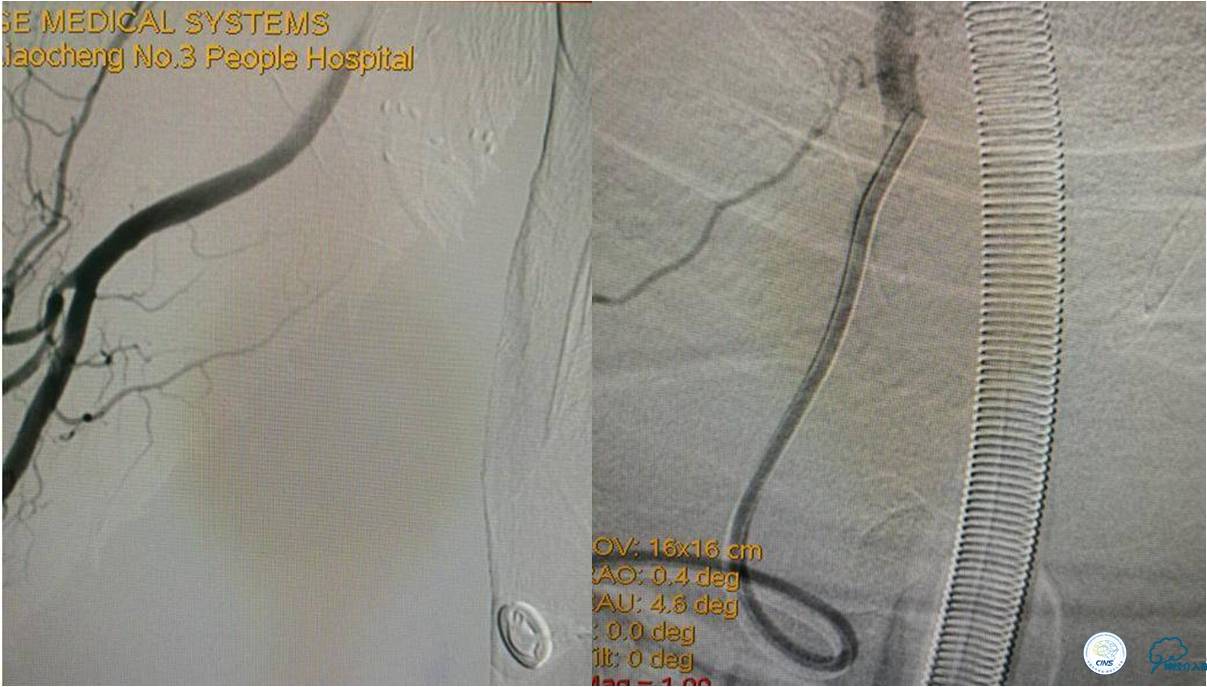

发病5.5小时给予股动脉穿刺

发现股动脉入路很差,考虑经桡穿刺。

》DSA资料(经桡动脉,5F导引导管)